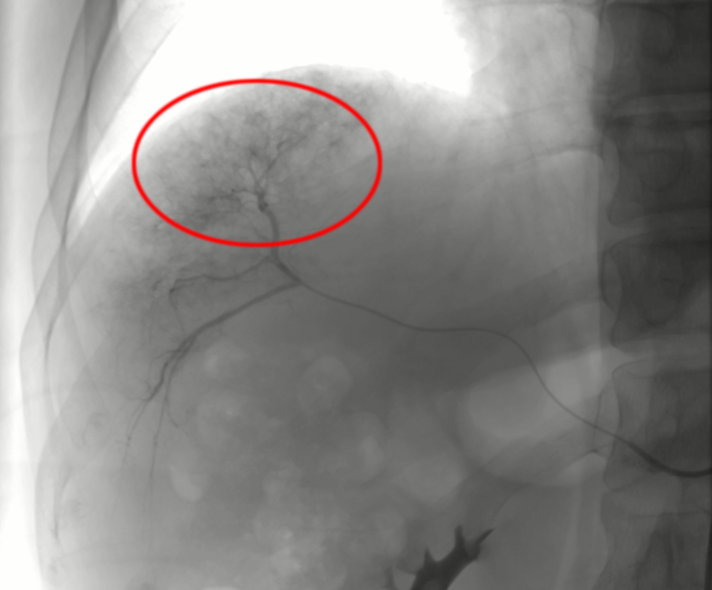

首先行TACE治療

肝動(dòng)脈造影后超選插管到肝癌供血?jiǎng)用},并通過導(dǎo)管向供血?jiǎng)用}注射化療藥物和栓塞劑。

肝動(dòng)脈栓塞化療結(jié)束后再次造影:肝癌染色消失,栓塞腫瘤的供養(yǎng)血管,以盡量使腫瘤去血管化。